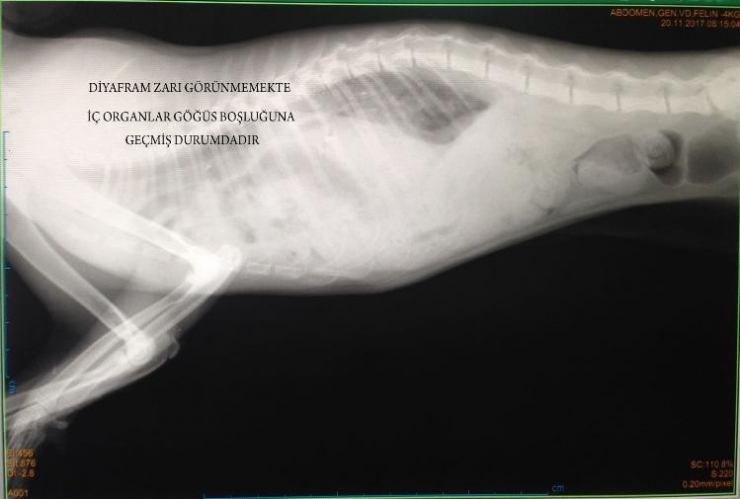

Yaklaşık 2 saat süren ameliyatla ilgili bilgi veren ERÜ Veteriner Fakültesi Cerrahi Anabilim Dalı Öğretim Üyesi Prof. Dr. Gültekin Alan, "Yaptığımız klinik incelemede hastanın karın solunumu yaptığı, soluk alışverişinde ciddi bir güçlük olduğunu gözlemledik. İleri tetkik amacıyla yaptığımız röntgen bulgularında da, karın organlarının göğüs boşluğu içinde olduğunu tespit ettik ve acilen hastanın operasyonuna karar verdik. Aynı gün yaptığımız operasyonda, ki bu kompleks bir operasyondu, yırtılan diyafram bölgesi dikildi ve hastanın tekrar eski sağlığına kavuşması sağlanmış oldu" diye konuştu.